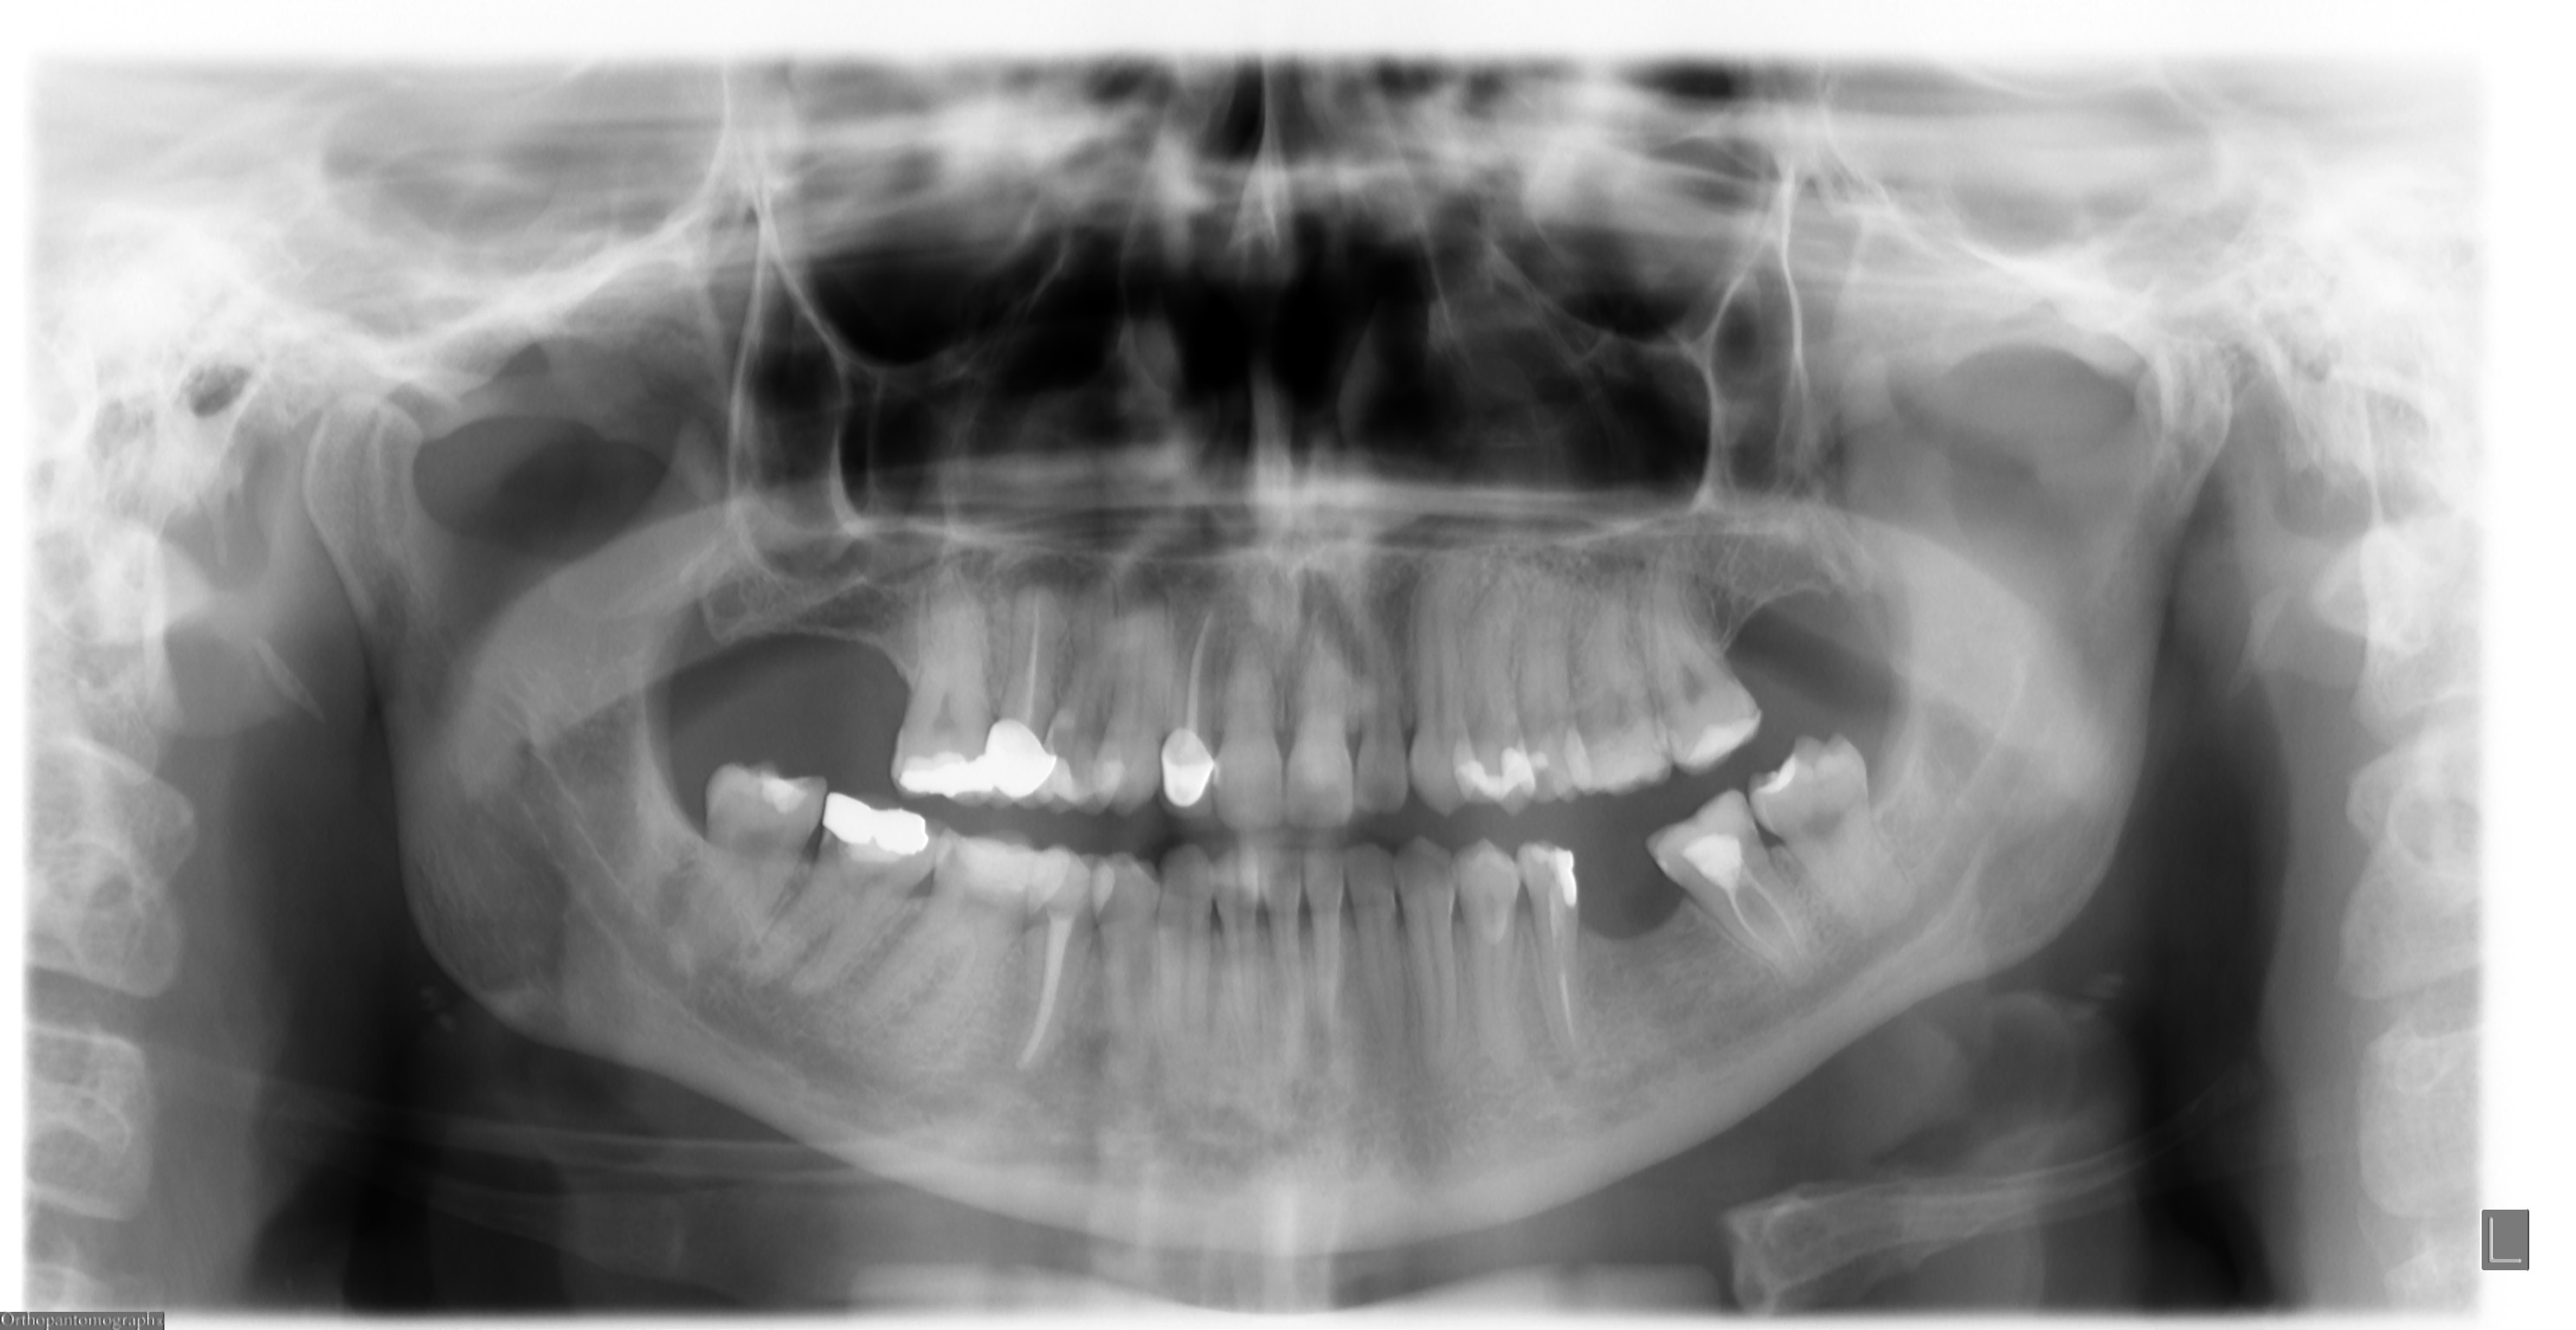

SEGUITO ALLA DOMANDA: Vorrei chiedere un chiarimento per quanto riguarda il referto di una ortopanoramica

Salve...sono quella di prima della lieve rarefazione apicale su 15. Il dente è coperto con una corona! Dovrò quindi spaccare la corona e ridevitallizarlo..poi dovrò rifare la corona immagino..quanti soldi! Ma scusate, il dentista che mi ha incapsulato questo dente, non aveva il dovere di fare una piccola rx per vedere che il dente fosse stato devitalizzato in maniera corretta (dal precedente odontoiatra) ? Grazie per la risposta. Patty P.S. Allego panoramica...

Gentile Sig.ra Patty, sarebbe stato certamente opportuno eseguire una Rx endorale prima di procedere alla protesizzazione del 1.5, ma, non conoscendo la sua specifica richiesta al suo nuovo dentista ed il tempo trascorso dalla precedente devitalizzazione non saprei dirLe di più. A prima vista la terapia canalare dall'OPT (poco affidabile,c mq, per tale tipo di accertamento)sembrerebbe che sigilli bene fino all'apice della radice. Le consiglio di esternare il suo problema (sempre se c'è dal punto di vista soggettivo) con il suo nuovo dentista che ha eseguito la corona al dente in questione. Cordiali saluti

Cara patty sicuramente avrebbe fatto meglio a fare una rx comunque non c'è problema, dalla radiografia sembra ci sia una zona osteolitica sopra quel dente ma non è molto ben definita tuttavia le cure canalari sembrano ben eseguite distinti saluti